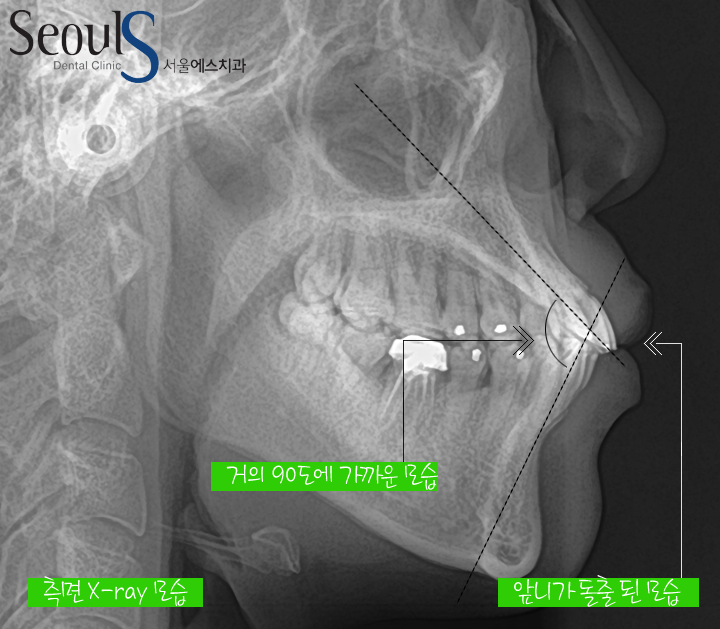

측면 X-ray 모습입니다

앞니가 튀어나왔고 입도 튀어나와보입니다

그리고 아래위 앞니에 선을 그엇을 때 만나는 부분의 각도가 90도에 가까운 모습인데

정상 각도는 120도 정도기 때문에

교정치료로 개선을 해주면 좋을거라 판단했고

교정진단을 했습니다